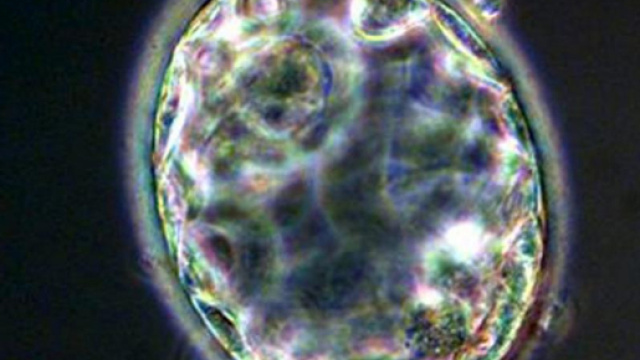

Cellule staminali riprogrammate nell’embrione di pecora

Secondo quanto annunciato, per realizzare l’ibrido è stato necessario inserire cellule staminali adulte “riprogrammate” in un embrione di pecora, fatto poi crescere per 28 giorni di cui 21 all’interno dell’utero di un animale. Si tratta del periodo massimo per cui l’esperimento era stato autorizzato. Secondo uno degli scienziati, Pablo Ross, nel periodo di crescita dell’embrione si sono riprodotte anche le cellule umane: tuttavia, per poter arrivare a un intero organo è necessario che il rapporto delle cellule umane scenda a una su 100.